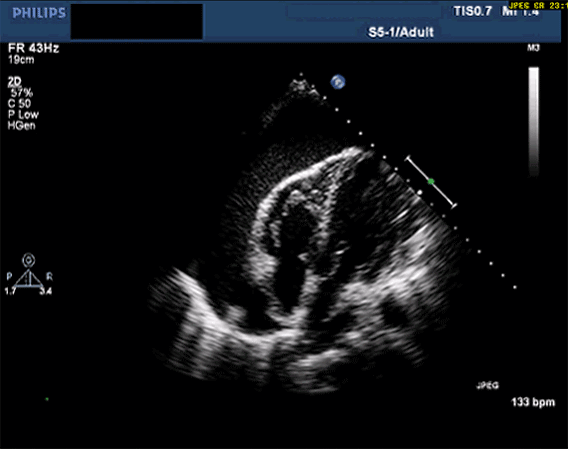

👉 Yatak başı USG şarttır, gecikmeden perikardiyosentez planlanır.

1️⃣ Büyük Perikardiyal Effüzyon / Kardiyak Tamponad

Mekanizma: Kalp, sıvı dolu perikard içinde mekanik olarak ileri–geri sallanır → depolarizasyon vektörü değişir → QRS alternansı oluşur.

Elektriksel alternans + hipotansiyon, juguler venöz dolgunluk, boğuk kalp sesleri =

👉 Tamponad güçlü olasılık -

Acil eylem: